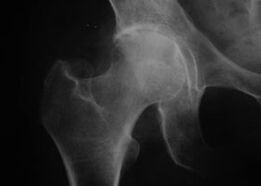

Coxathrosis, csípőízület arthrosis

Ezzel a betegséggel az arthrosis klasszikus klinikai képe figyelhető meg.

A coxarthrosis első tünete a fizikai aktivitás utáni kellemetlen érzés a csípőízületben.

Progresszív coxarthrosis esetén a fájdalom fokozódik, merevség és mozgáskorlátozottság jelenik meg.

A súlyos coxarthrosisban szenvedő betegek kímélik az érintett végtagot, kerülik a rálépést, és álló helyzetben olyan testhelyzetet választanak, amelyben a fájdalom a legkevésbé érezhető.